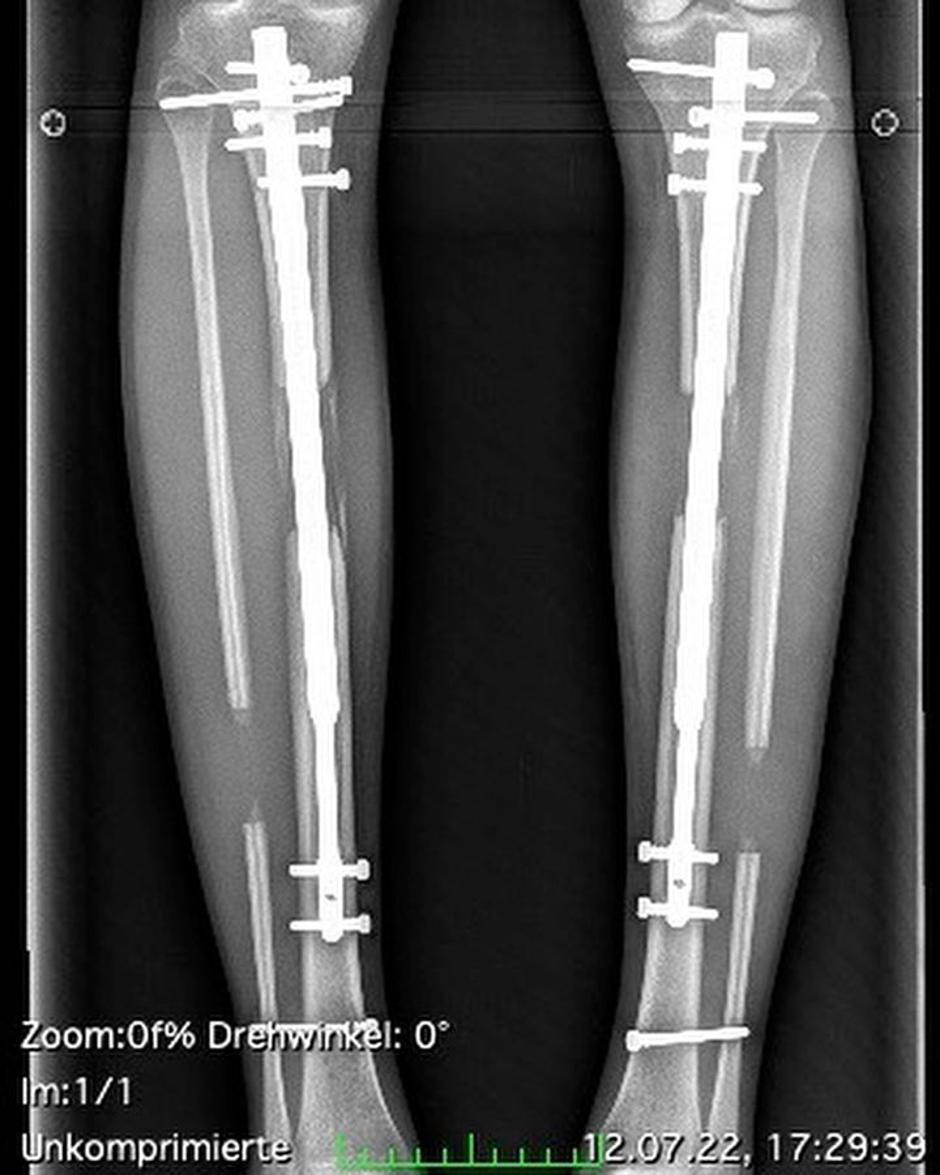

Nemška manekenka Theresia Fischer, znana iz šova Germany's Next Topmodel, si je dala podaljšati noge. Prestala je dve operaciji in "zrasla" za 14 centimetrov. Sedaj je visoka 184 centimetrov, idealna višina za delo v svetu mode. Za poseg je plačala 140 tisoč evrov.

"8,5 cm + 5,5 cm = 14 cm!! Od moje druge operacije je minilo eno leto. Leto polno moči, energije in vzdržljivosti. Leto brez visokih petk. Leto, ki je spremenilo moje življenje," je bila sprva navdušena, sedaj pa priznala, da je bil poseg napaka. Bolečin še vedno ni pozabila ... "Jemati sem morala velike količine opiatov. Na trenutke nisem več vedela zase," je razkrila lepotica, pri kateri so se po operaciji pojavili nevarni zapleti - kar dvakrat je prišlo do okužbe v kosteh. Od operacije je minilo že eno leto, posledice pa občuti še danes, med drugim se vsako jutro zbuja zaradi krčev. "Moja hoja je za zdaj še trda, a to se bo izboljšalo, ko bodo marca 2024 odstranili palice," je razložila.

Med zapletenim posegom marca 2022 so 30-letnici prežagali kosti spodnjega dela noge in ji z obeh strani vstavili palice, s katerimi si je lahko nato samostojno z navijanjem podaljševala noge - centimeter za centimetrom. "Ko sedaj pri 31 letih pomislim za nazaj, se vprašam: 'Theresia, kako slabo si se morala počutiti oziroma v kakšni situaciji si se takrat znašla, da si se spustila v to?'"